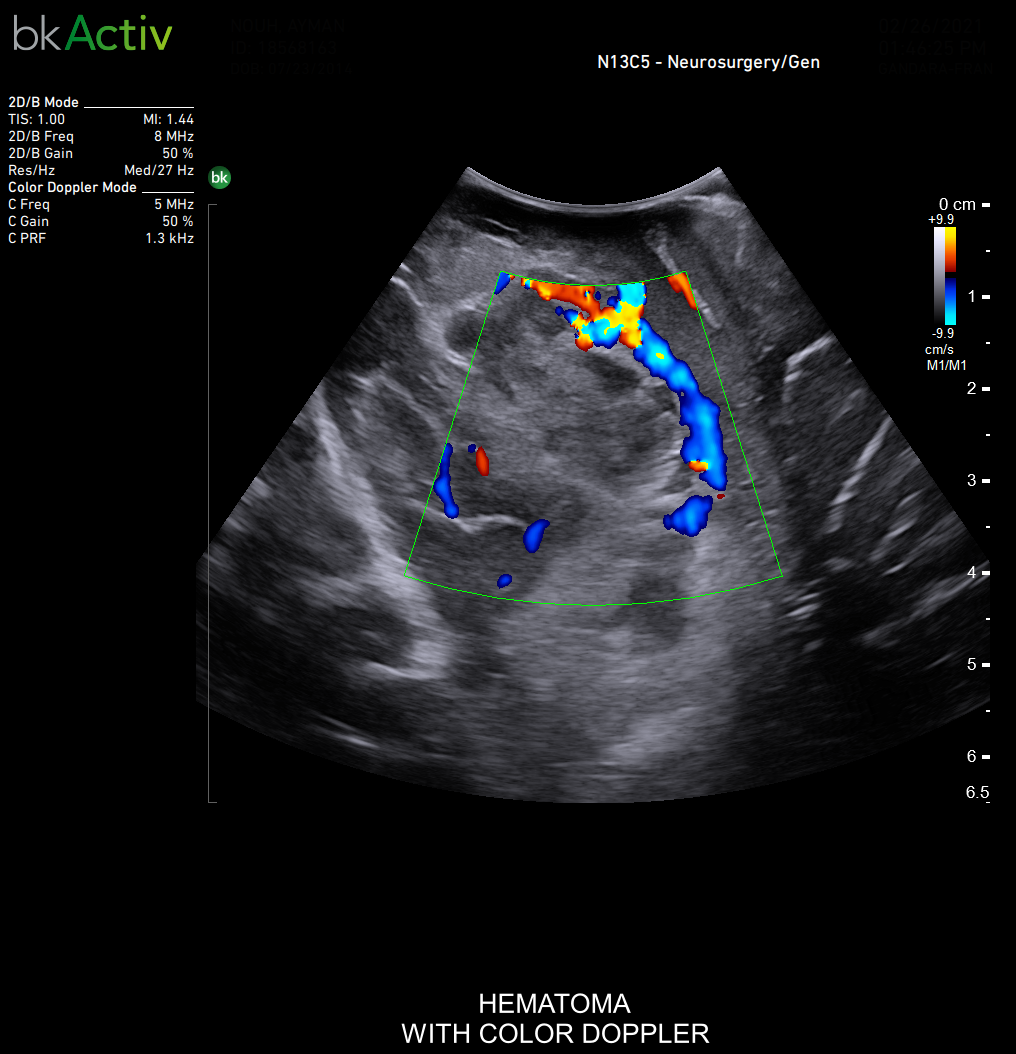

Neurosurgery and Spine

Improved algorithms that automatically allow uniform image resolution, greater details around lesion borders and at larger depths, and enhanced penetration, spatial resolution, and near field image quality.